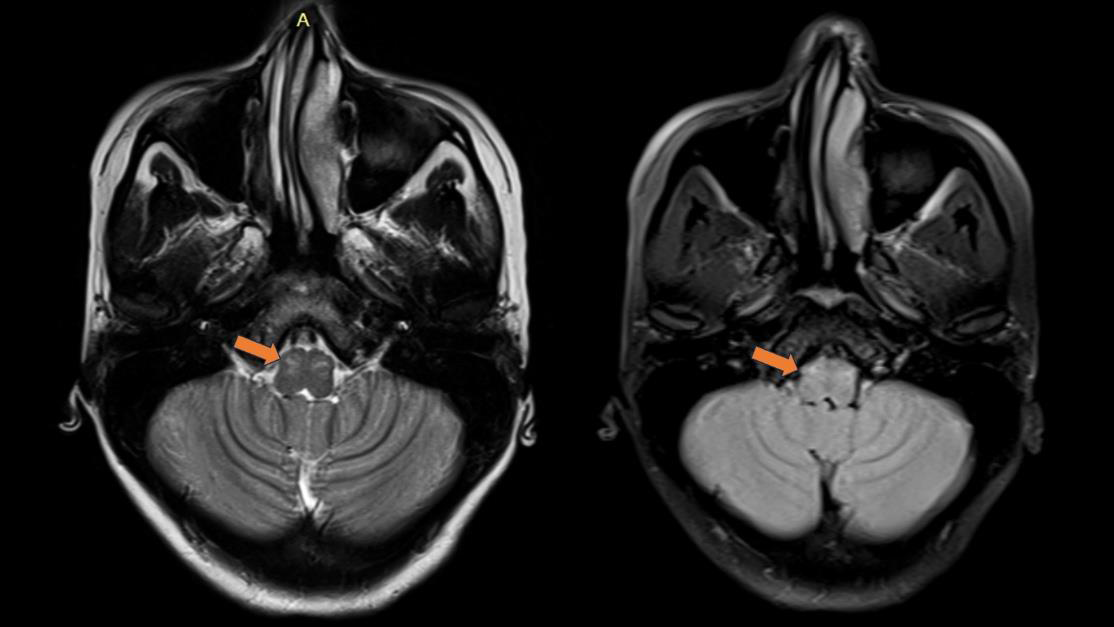

Figure 1:MRI Brain(T2/FLAIR): Bilateral symmetric hyperintense lesions

involving midbrain and substantia nigra.

The extrapyramidal signs—including rubral tremors, rigidity,

and dystonia—suggest involvement of the basal ganglia or midbrain

tegmentum, a region frequently implicated in EBV encephalitis, as